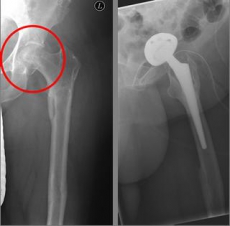

Oberschenkel 3

Picture: This picture shows the treatment of a severely displaced fracture with a so-called duo head prosthesis. The acetabulum was left here.

In older age and with stronger displacement of the fracture can be done by a duo-head prosthesis. Here only the femoral head is replaced, the hip socket is preserved. In case of simultaneous hip arthrosis, a total endoprosthesis (hip replacement) with replacement of the acetabular cup can be used.